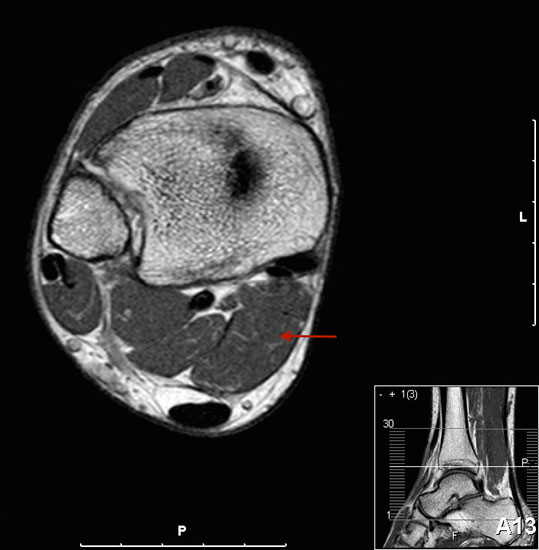

MR-tomographische Darstellung eines unspezifischen weichteiligen Raumforderug im Bereich des dorso-lateralen Rückfußes. Die offene Probebiopsie ergab schließlich die Diagnose eines hochmalignen Synovialsarkoms.

Abbildung 34

10% aller Patienten mit Weichteilsarkomen weisen bei Erst­diagnose bereits Metastasen auf, meist in der Lunge. Drei Viertel der Weichteilsarkome zeigen eine schlechte histo­logische Differenzierung („high-grade“, G3 und G4) und die Letalität beträgt insgesamt über 30%. Trotz des vergleichs­weise seltenen Vorkommens (<1% aller Malignome) gilt diesen Entitäten aufgrund der schlechten Prognose erhöhte Aufmerksamkeit. Das Synovialsarkom ist der häufigste maligne Weichteiltumor im Bereich des Fußes und betrifft hier typischerweise Adoleszente und Erwachsene in der 2. bis zur 5.Lebensdekade (Abb. 34). Zwischen Beginn der Symptome und endgültiger Diagnose­stellung vergehen durchschnittlich 21 Monate. Das Synyovialsarkom zeigt einen unspezifischen klinischen Verlauf mit variabler Wachstumsge- schwindigkeit und kann zahlreiche andere Entitäten imitieren 50. Die Gefahr sowohl pulmonaler/hämatogener als auch lymphogener Metastasen ist hoch.